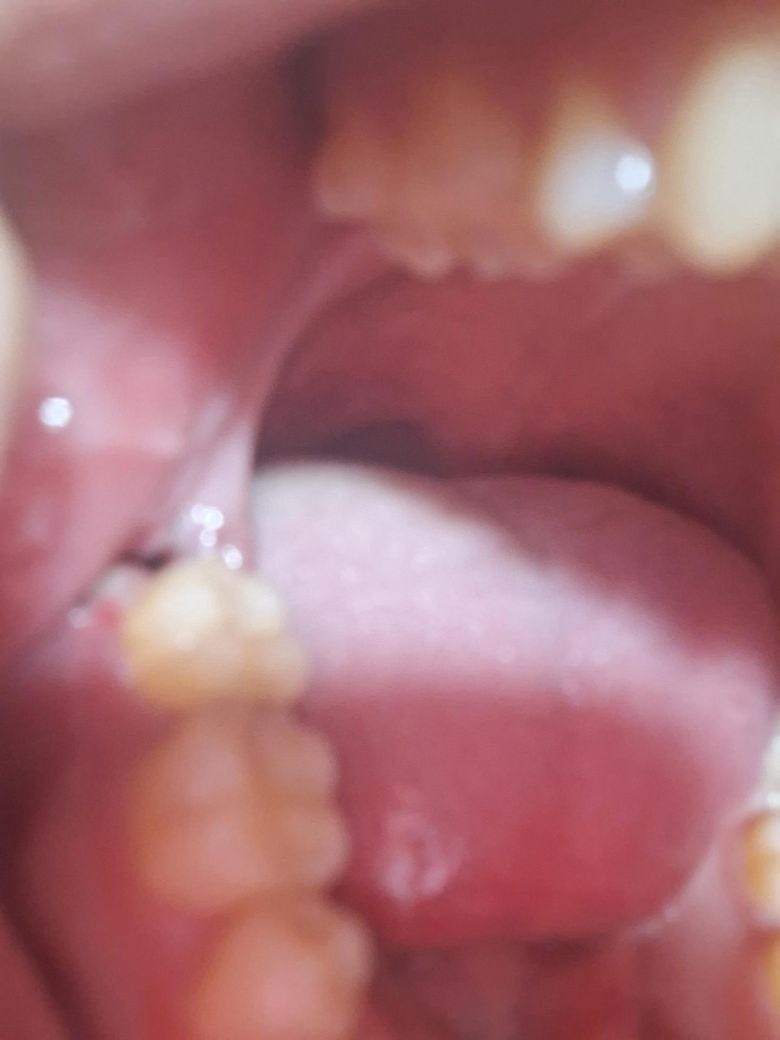

뭔가 역한 냄새도 없고 통증도 엄청 아프진 않고 가끔 욱신 거리는 느낌인데

혹시 몰라서 사진 찍어보니까 이러네요 혹시 드라이소켓인가요 ?

드라이소켓은 애매한 통증이 아닙니다 누가 느껴도 극심한 통증입니다 지금 상황은 크게 문제 없어보입니다

사진으로 봤을 경우에는 드라이소켓으로 보이지는 않습니다. 드라이소켓이 있을 경우 극심한 통증과 냄새가 나는 경우가 많이 있습니다. 드라이소켓이 생기는 원인은 발치한 부위의 혈병이 제거가 되기 때문이기 때문에 발치한 부위가 자극되지 않도록 하는 것이 좋습니다.

드라이소켓이라면 극심한 통증 동반되며 첨부한 사진에서는 큰 이상 소견 보이지는 않습니다. 정상치유 과정중인 것으로 보이며 아직 완전 치유된 상태 아니기 때문에 물양치 잘하며 관리잘하시기를 바랍니다.